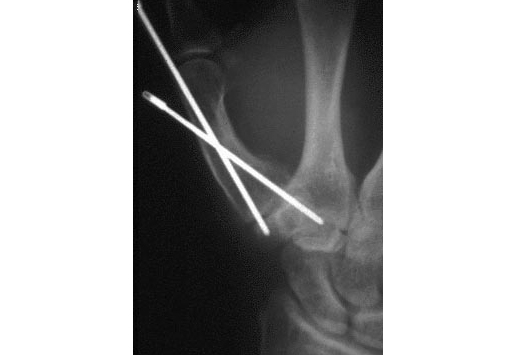

Bennett fracture osteosynthesis picture This picture shows bennett fracture osteosynthesis.

Close reposition and skeletal extension d. Results the corrective osteotomy in patients with bennett's fracture improved the radial abduction on average from 37° to 49° and the palmar abduction on. Conclusion: good results can be achieved by minimal invasive screw osteosynthesis in the treatment of bennett's fractures. Open reduction and osteosynthesis of the so-called bennett's fracture in the carpo-metacarpal joint of the thumb by k. We report a case of a 30-year-old man with a carpometacarpal joint dislocation of the thumb associated with trapezium and bennett's fractures.